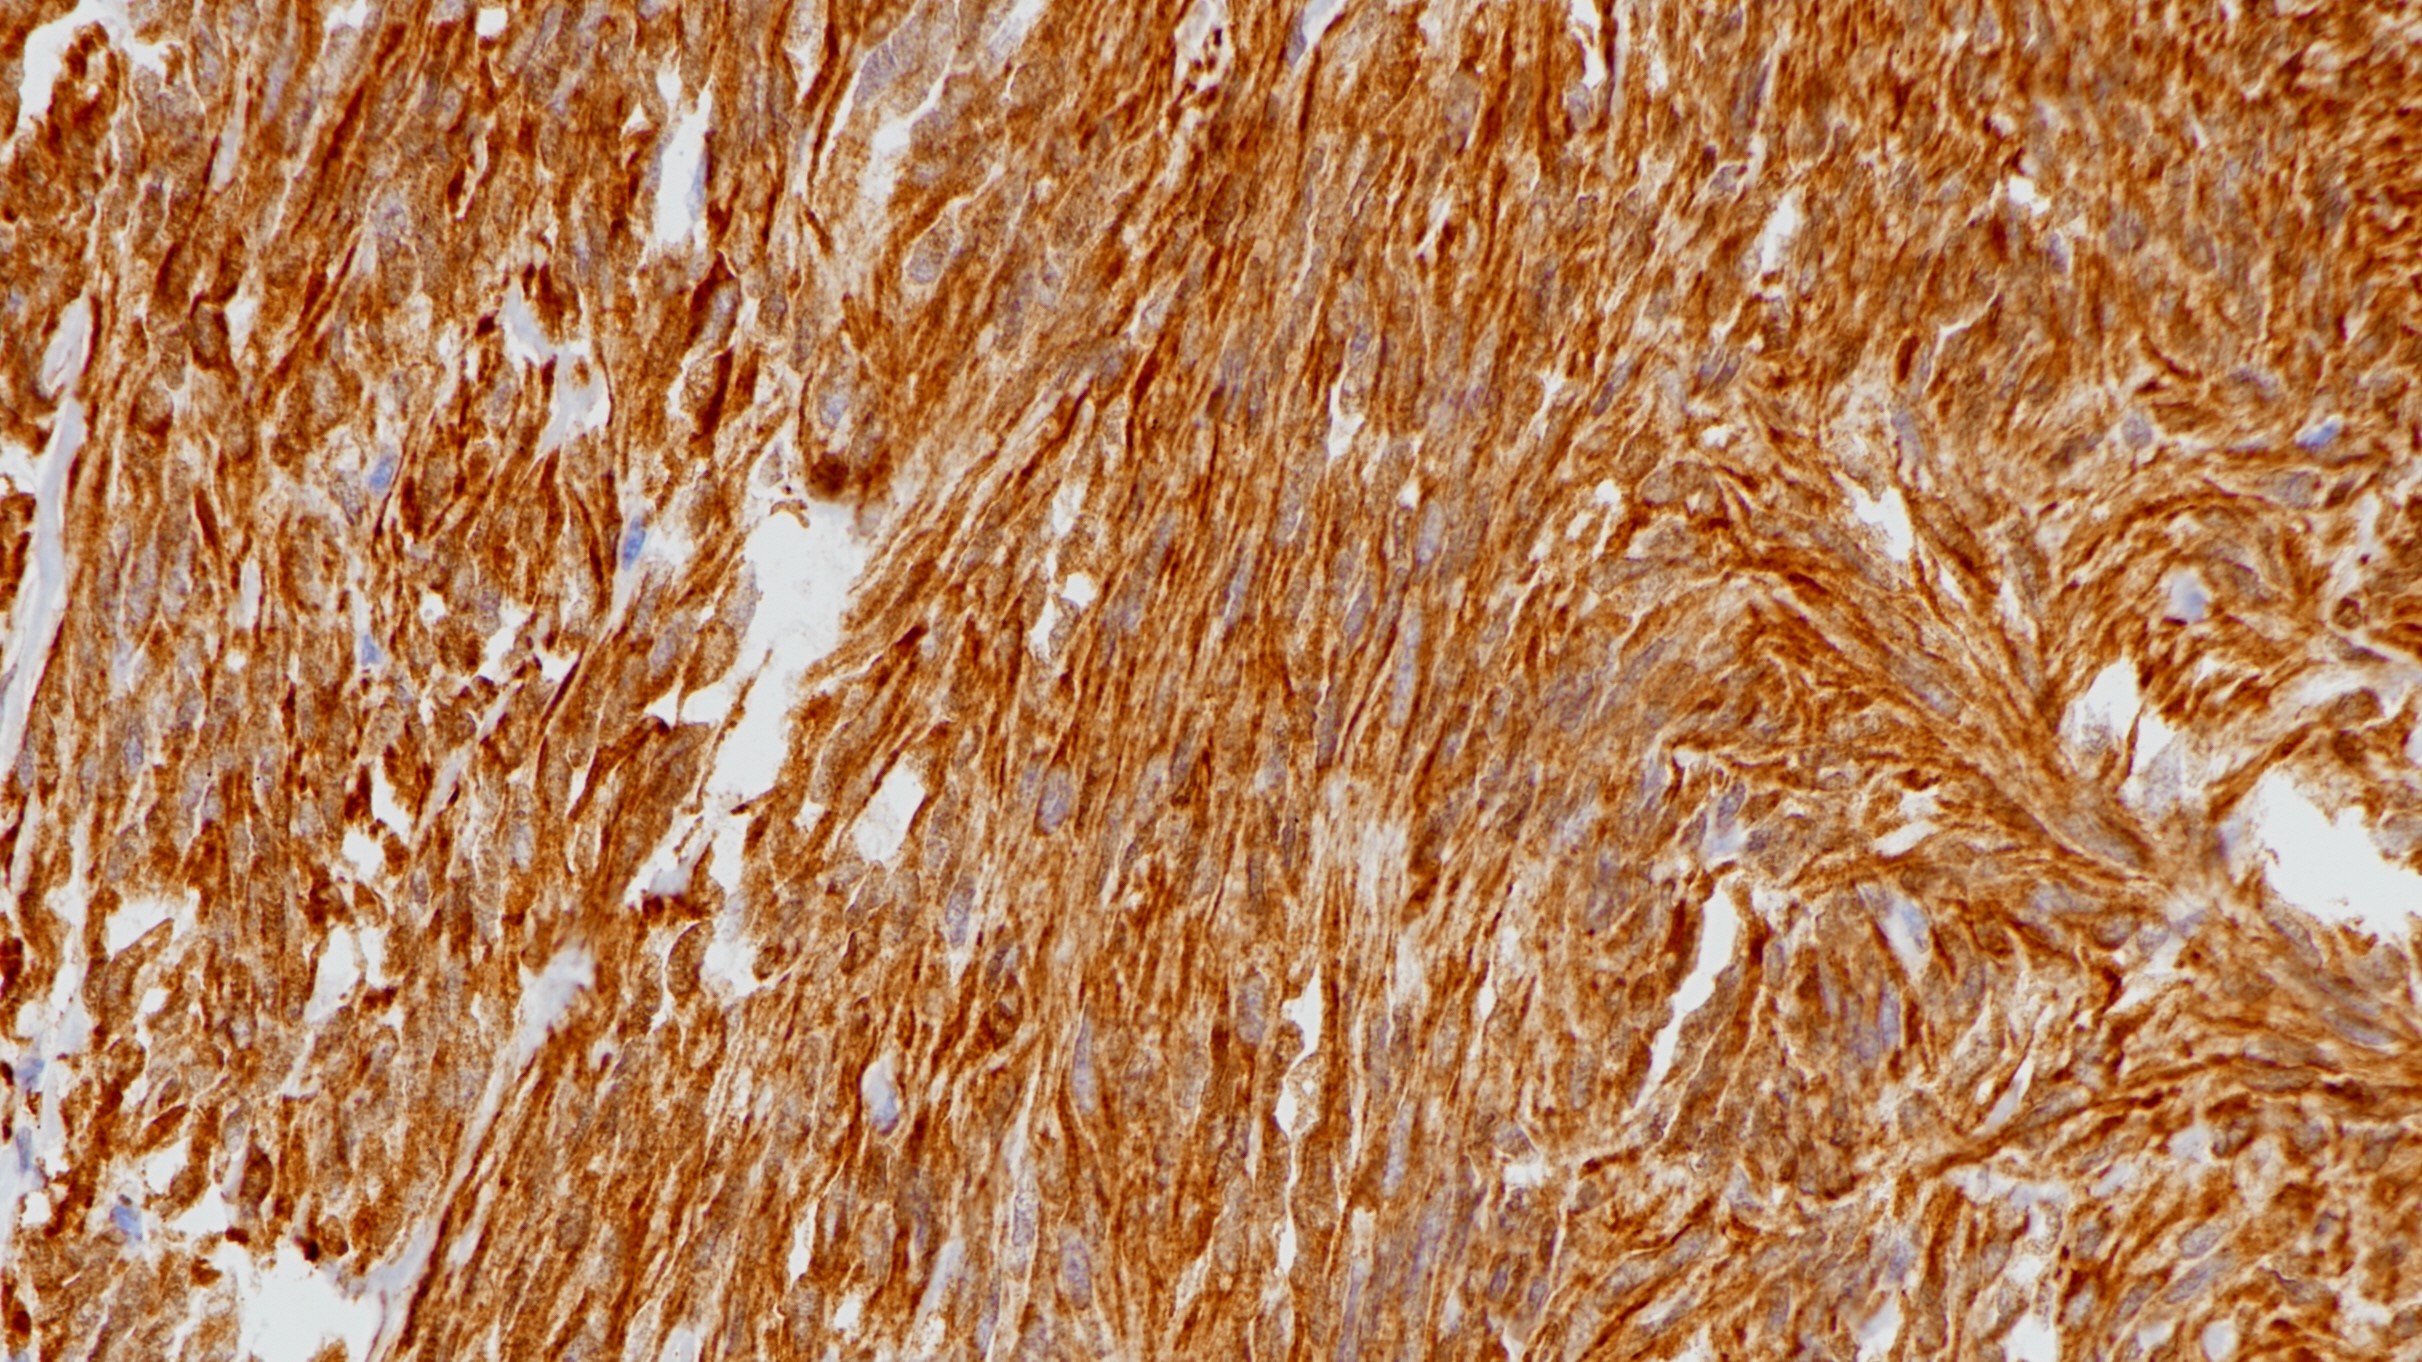

1.Characterization of OCT3/4, Nestin, NANOG, CD44 and CD24 as stem cell markers in canine prostate cancer.[J]. Costa Camila Dorotea,Justo Andre Augusto,Kobayashi Priscila Emiko,Story Michelle M,Palmieri Chiara,Laufer Amorim Renée,Fonseca-Alves Carlos Eduardo. The international journal of biochemistry & cell biology